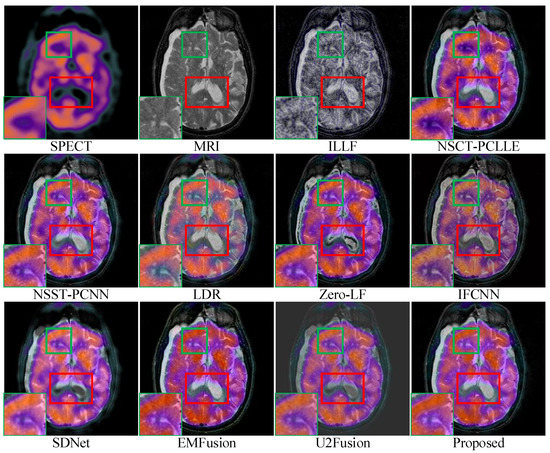

4.3. Subjective Quality Assessment

| Objective evaluation of performance for images in Figure 6 | ILLF | 0.3732 | 0.8035 | 0.0547 | 0.0167 | 4.6800 | 0.0095 |

| NSST-PCNN | 0.6509(2) | 0.8078(2) | 1.4767(2) | 0.4576 | 5.8536 | 0.2977 | |

| NSCT-PCLLE | 0.6040 | 0.8069 | 1.3982(3) | 0.4276 | 5.9460(3) | 0.2982(3) | |

| LRD | 0.5225 | 0.8060 | 0.2486 | 0.3397 | 6.4027 | 0.1808 | |

| Zero-LF | 0.6229(3) | 0.8074(3) | 0.3195 | 0.4543 | 5.6813 | 0.2352 | |

| IFCNN | 0.6073 | 0.8072 | 0.2155 | 0.4949(2) | 5.8007 | 0.2461 | |

| SDNet | 0.6062 | 0.8057 | 0.1035 | 0.2804 | 5.0403 | 0.1451 | |

| EMFusion | 0.5906 | 0.8072 | 0.2717 | 0.5669 | 5.8329 | 0.2688 | |

| U2Fusion | 0.5653 | 0.8055 | 0.0879 | 0.3689 | 5.0805 | 0.3071(2) | |

| Proposed | 0.8319 | 0.8129 | 1.9020 | 0.4902(3) | 6.2604(2) | 0.3170 | |